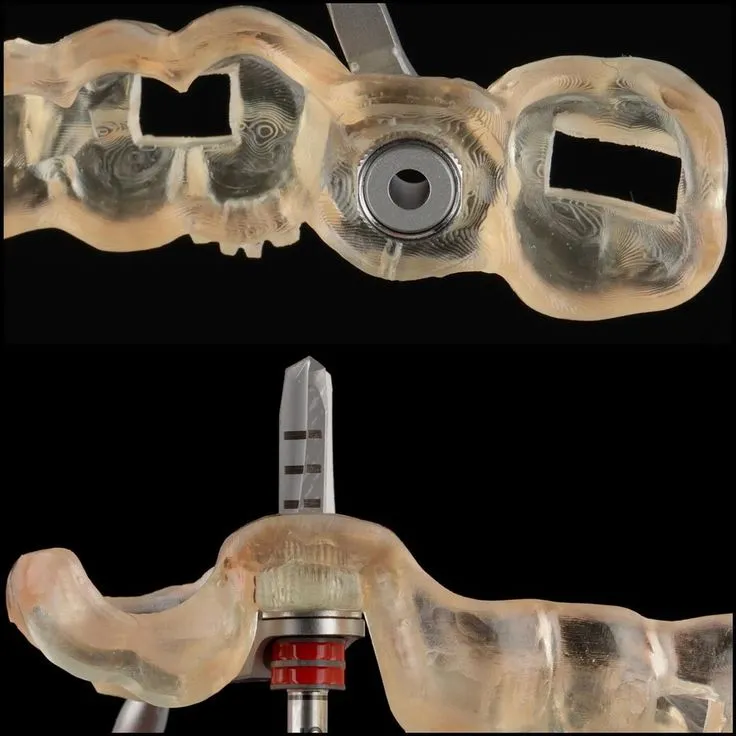

Conception 100 % numérique pour une précision maximale

Nous utilisons un flux de travail numérique complet, de la réception des fichiers à la fabrication finale :

- Importation directe des fichiers STL / scan intraoral du praticien

- Modélisation assistée par ordinateur (CAO spécialisée pour implantologie)

- Prise en compte des axes implantaires, émergences, piliers et angulations

- Conception de guides chirurgicaux, armatures, et chapes sur mesure

- Validation esthétique en amont avec prévisualisation 3D du projet prothétique